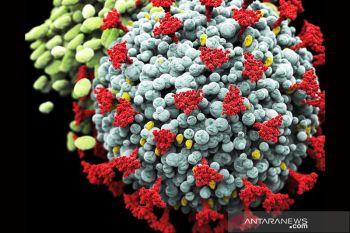

Kementerian Kesehatan Senegal mengonfirmasi satu kasus demam berdarah Krimea-Kongo (CCHF) di salah satu rumah sakit di ...

Bupati Garut Rudy Gunawan mengingatkan masyarakat untuk meningkatkan kewaspadaan terhadap penularan COVID-19 yang sejak ...

Satuan Tugas Penanganan COVID-19 mencatat penerima vaksinasi COVID-19 dosis penguat atau booster pertama hingga Rabu, ...

Juru Bicara Kementerian Kesehatan RI Mohammad Syahril mengajak masyarakat untuk kembali disiplin memakai masker sebagai ...

Kementerian Kesehatan mengimbau masyarakat tetap memakai masker dan menjalani hidup sehat untuk mencegah potensi ...

Kementerian Kesehatan RI meminta masyarakat mengaktifkan kembali protokol kesehatan 3M (memakai masker, mencuci tangan, ...

Juru Bicara Kementerian Kesehatan Mohammad Syahril mengatakan dua pasien terinfeksi subvarian Omicron XBB.1.16 atau ...